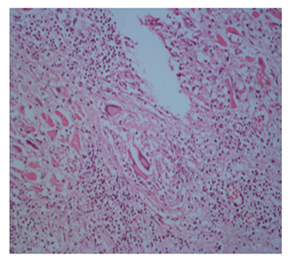

Our case was 34 years old male patient who had sudden loss of consciousness after discussing with another driver in traffic and he died on his way to hospital. The case brought to the Morgue Department of The Institute of Forensic Medicine of Adana, Turkey. Autopsy was performed and evaluated by two forensic medicine specialist and consulted to a pathologist. On internal examination, the heart weighed 340 g and thickness of left ventricular wall was 1,3cm, that of right ventricle was 0,1-0,3cm. Papillary muscles in both ventricles were fibrotic and showed disarrangement. Myocardial sections showed areas of fibrosis and dark-mottled areas. Microscopic examination of myocardial sections revealed connective tissue replacing normal myocardial muscle bundles; diffuse lymphohistiositic inflammatory cell infiltration, multinuclear giant cells (Figure 1). Microscopic sections of other internal organs showed no pathology other than hyperemia. On the basis of these findings, the final diagnosis was giant-cell myocarditis.

Figures 1 Myocardial lymphohistiositic inflammatory cell infiltration, multinuclear giant cells (HEX 100, HEX 200, HEX 400).